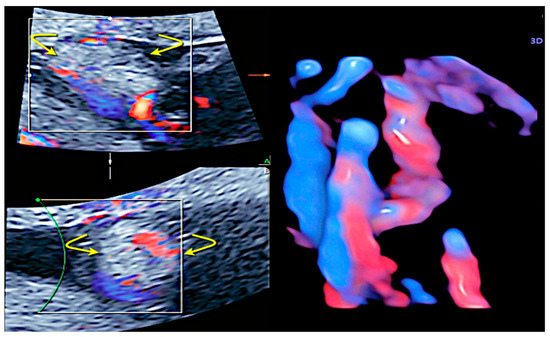

3.6. Umbilical Cord Cysts